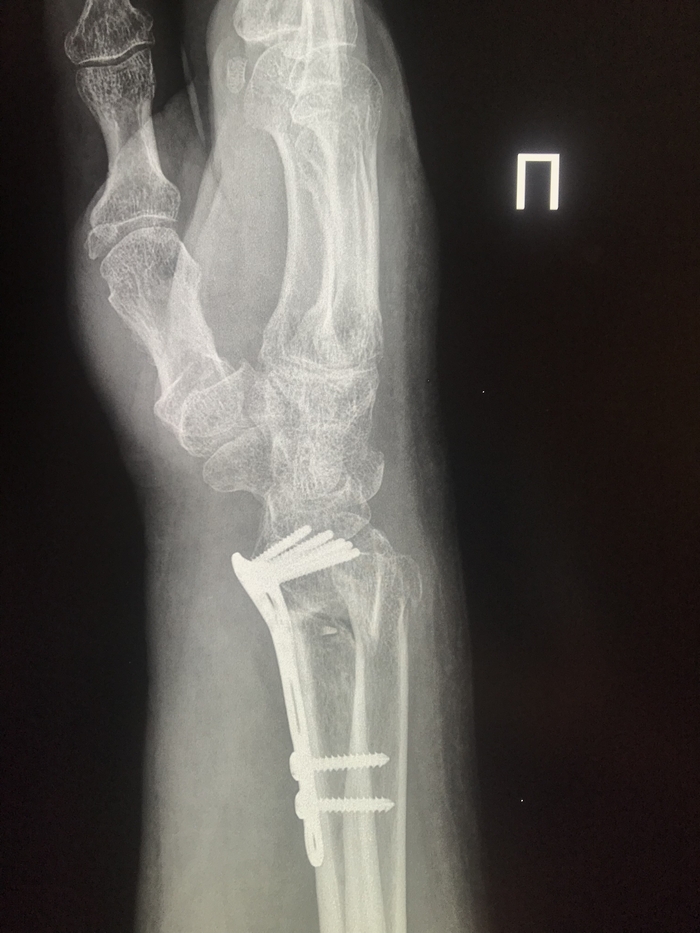

Другой пациент, тоже электросамокат, падение и результат.